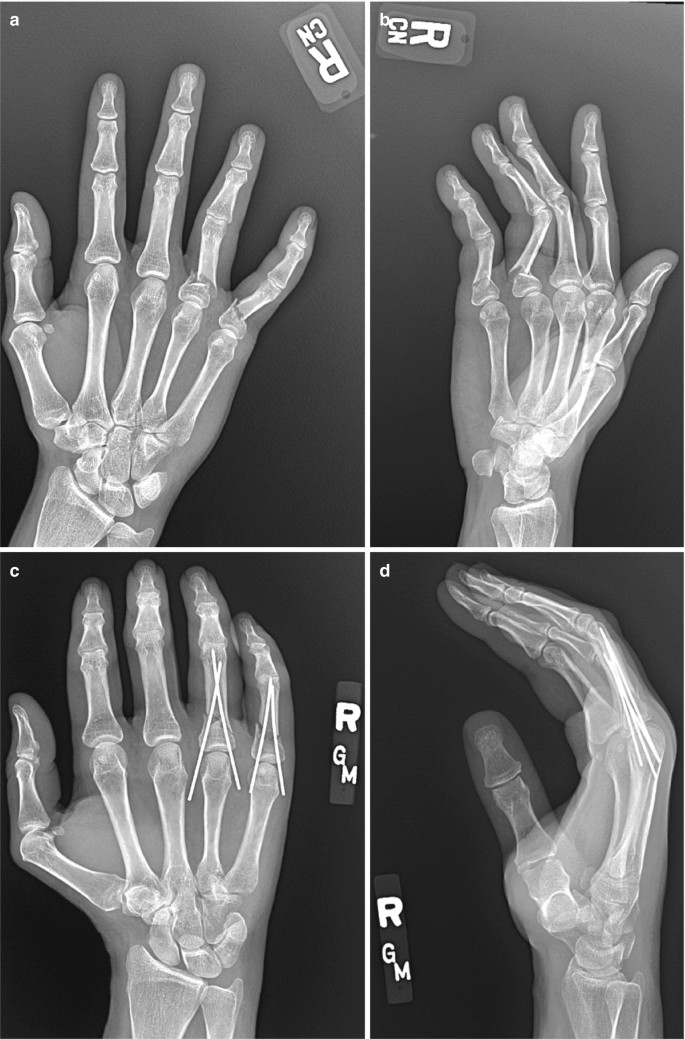

METACARPAL

Metacarpal adalah tulang di bagian tengah pada kerangka tangan yang terletak di antara tulang jari dan karpus yang membentuk hubungan dengan lengan bawah.

- Saat terjadi cedera atau trauma pada tangan yang melibatkan tulang metacarpal

- Untuk memeriksa patah tulang atau retak pada tulang metacarpal

- Ketika terdapat deformitas atau perubahan bentuk pada tangan

- Untuk mengevaluasi perkembangan atau penyembuhan setelah operasi tangan